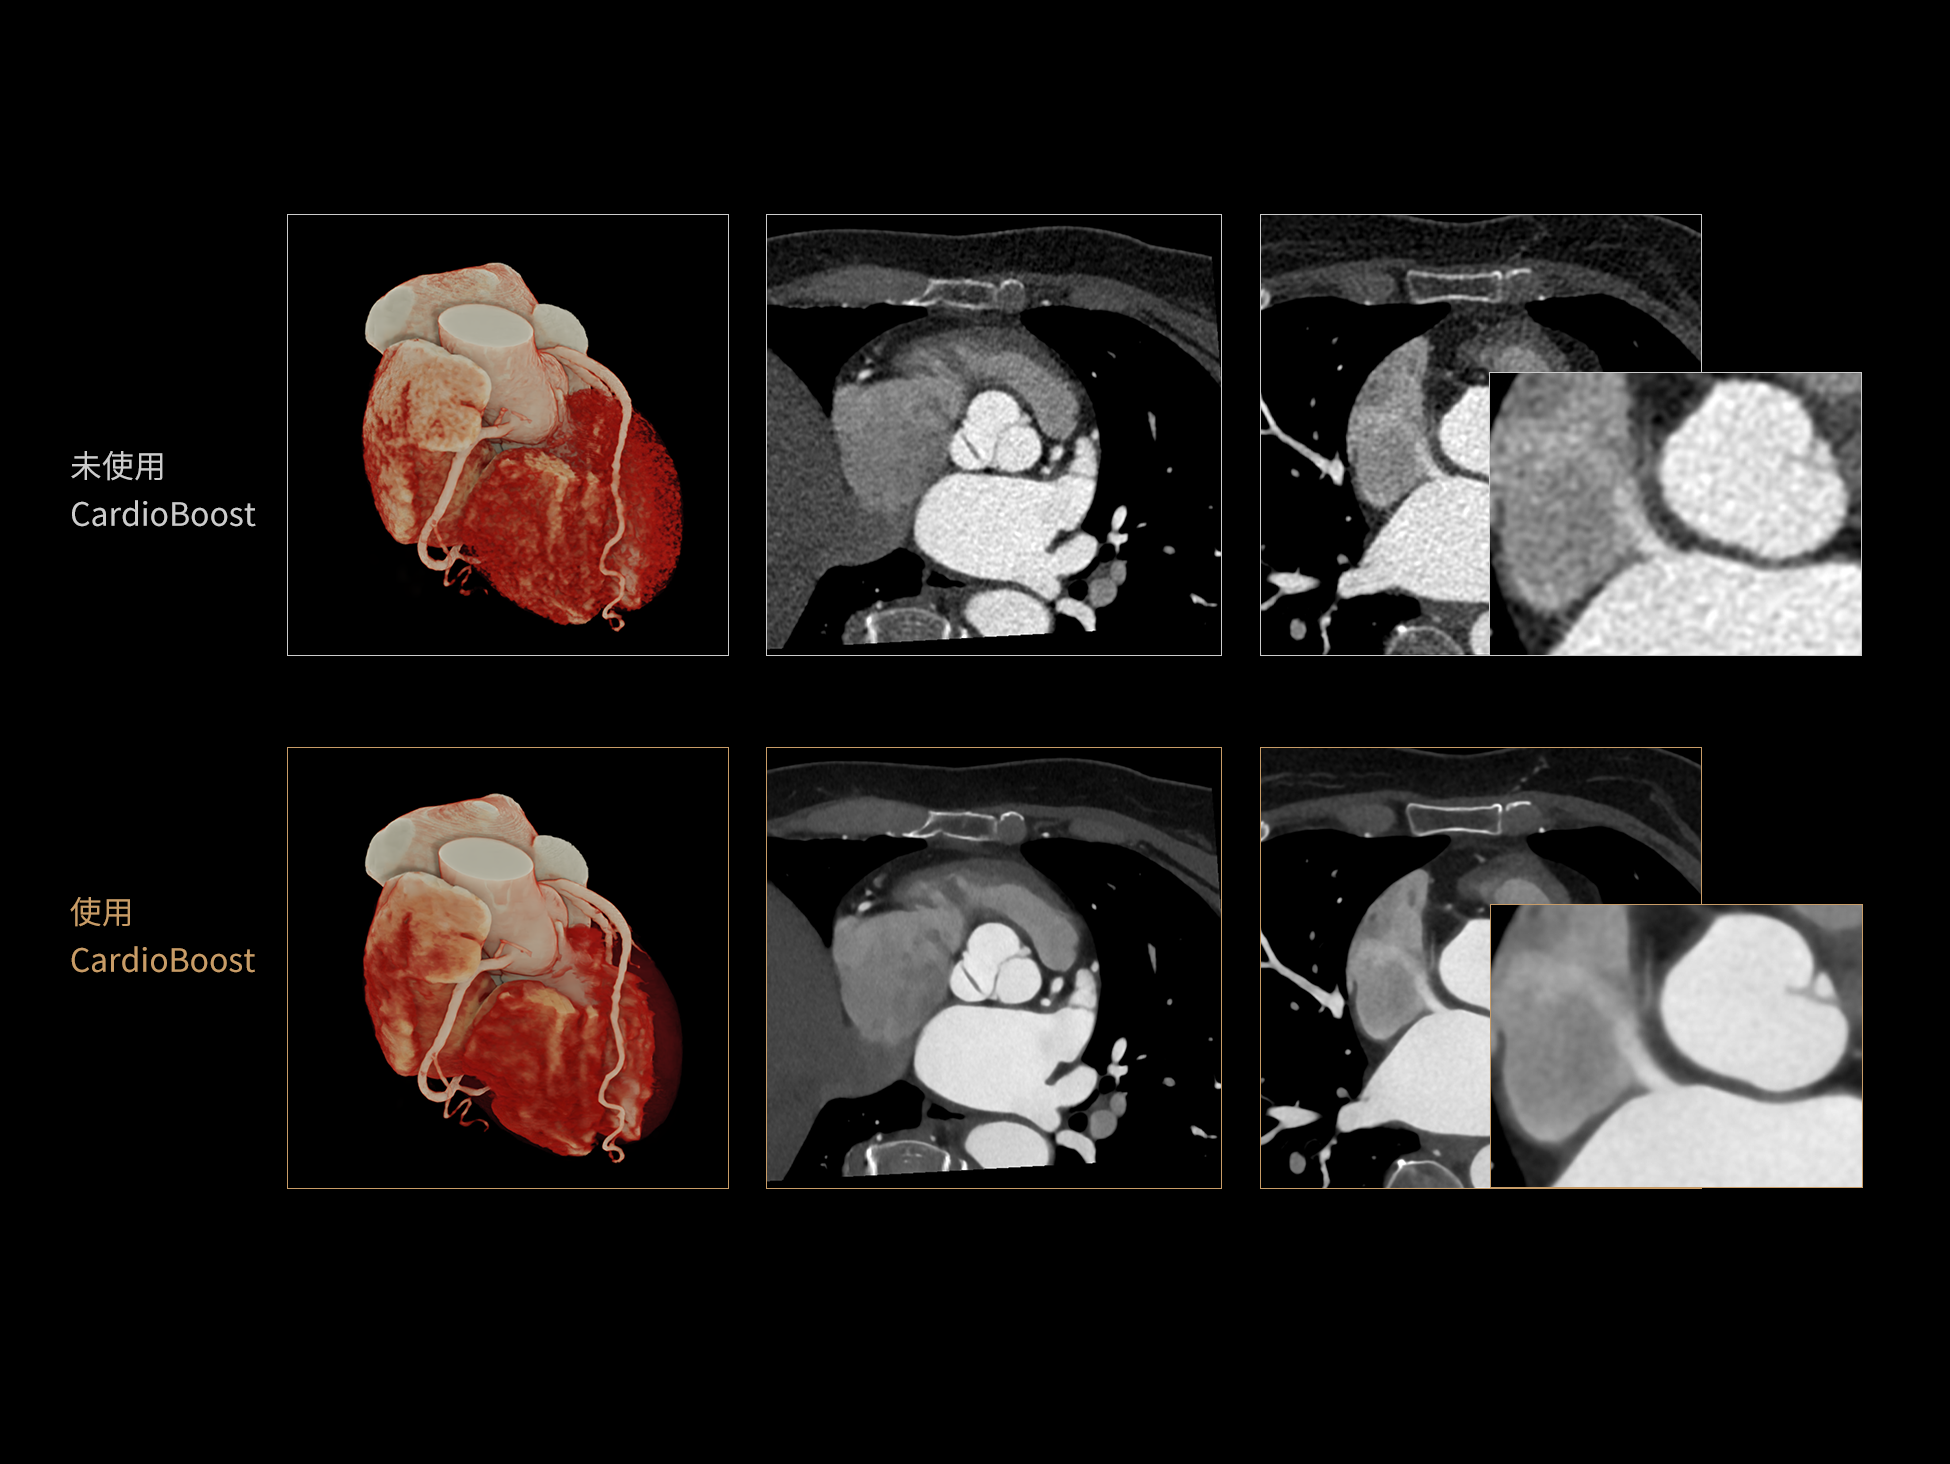

CardioBoost:专属网络设计,重塑心脏影像表现

目前心脏的 CT 检查还存在辐射剂量偏高、空间分辨率不足、 致密钙化伪影影响冠脉狭窄程度评估等方面的限 制[1][2]。CardioBoost 技术专为心脏 CT 高清成像而开发,通过 3D 神经网络的深度学习技术,利用先进的注意力机制在识别关键成像特征方面的出色表现,能够精确地聚焦于斑块、支架以及微小血管等关键细节,清晰展示这些结构与冠脉血管的边界,从而显著提高诊断的准确性,并提升医生的诊断信心。创新的 CardioBoost 心脏图像重建算法,不仅实现了图像清晰度的提升和伪影的去除,更能在减少辐射剂量的同时,保证心脏图像的高质量和图像纹理的自然。

采用 3D 神经网络的空间结构优势与精细的组织分类能力,CardioBoost 技术优化了组织对比,高清展示血管斑块,使斑块与血管边缘的轮廓清晰可辨,提升斑块诊断与评估的精确性。

借助 3D 神经网络设计、空间注意力机制聚焦与特征强化作用,CardioBoost技术提升图像的空间分辨率,实现冠脉支架的高清成像,对支架形态与管腔通畅度的评估更精准。

CardioBoost 整合先进的 3D 神经网络和空间注意力机制,大幅增强数据处理的速度与精确度。该技术能有效抑制由致密钙化引起的晕状伪影,清晰展现钙化斑块的原始结构和大小,对冠脉狭窄的评估更加精确可靠。